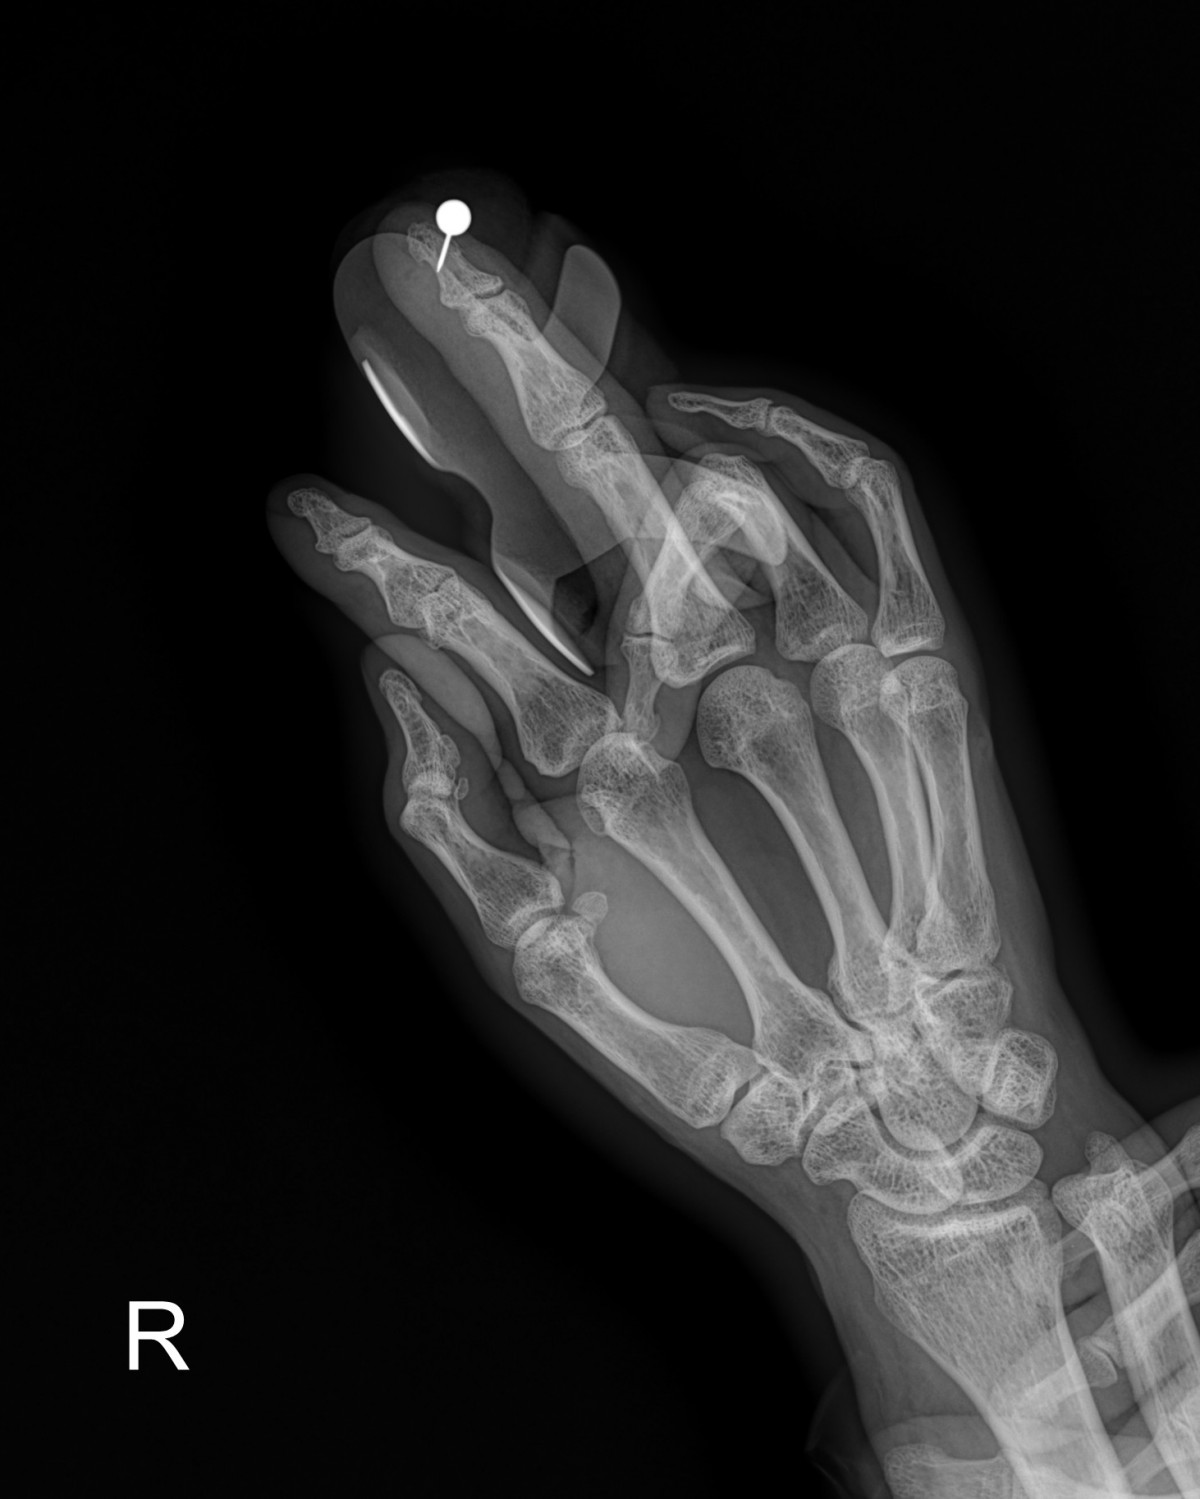

정지영원장님 손가락 골절 한철O 환자

dae765e4d9ac96aee867c9d6292d8784_1758008653_609.jpg